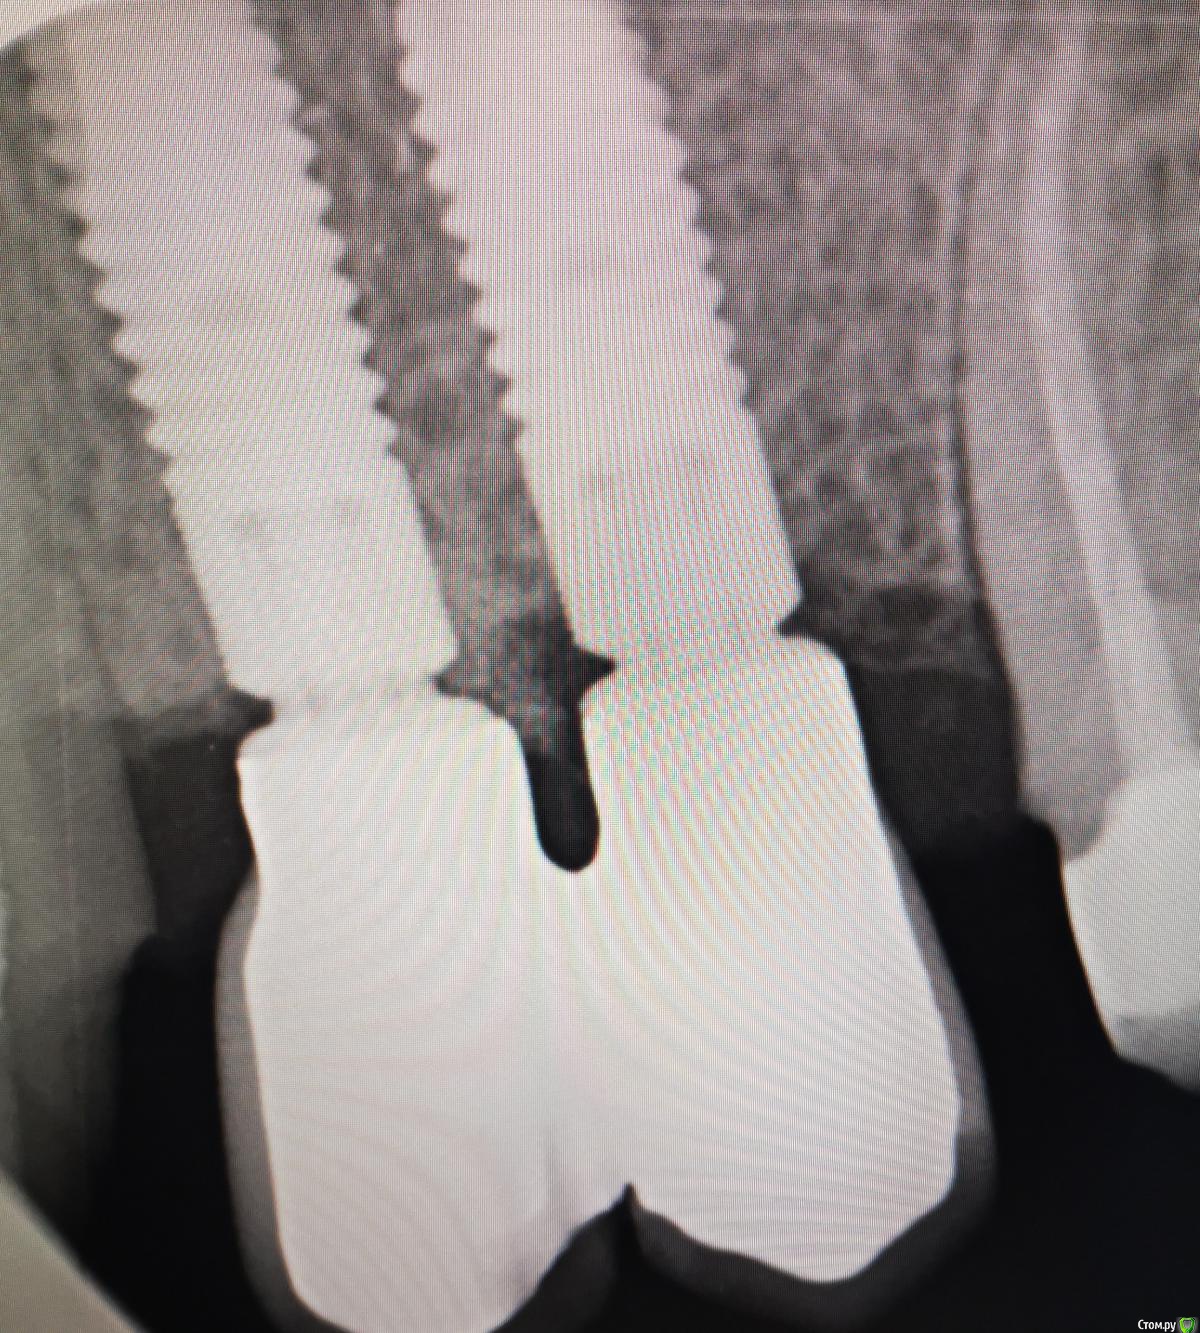

Тимур86 Опубликовано 15 октября, 2019 Поделиться Опубликовано 15 октября, 2019 (изменено) Вот такую убыль костной такни получили через 1.5 года после протезирования...Астра 4.0,костной пластики в области 25 не было,кости было хоть отбавляй,рг после протезирования идеальный,соматических заболеваний (вроде) нету. Откуда такая убыль за столь короткий срок? Изменено 15 октября, 2019 пользователем Тимур86 Ссылка на комментарий

red_butler Опубликовано 15 октября, 2019 Поделиться Опубликовано 15 октября, 2019 Расстояние между винтов 1,5-2 мм? Может нарушение трофики привело к некрозу? Ссылка на комментарий

Тимур86 Опубликовано 15 октября, 2019 Автор Поделиться Опубликовано 15 октября, 2019 Со всех сторон одного импланта? С дистальной даже больше... 24 удалил потому что при кюретаже лунки 25 появился щелевидный дефект кости между 24-25 толщиной 1мм,т.е. 24 практически полностью в кости был! Не думаю... Ссылка на комментарий

krokomot Опубликовано 15 октября, 2019 Поделиться Опубликовано 15 октября, 2019 Простите, а где убыль костной ткани на снимке? Прицельный есть перед удалением? Ссылка на комментарий

Santi Опубликовано 26 октября, 2019 Поделиться Опубликовано 26 октября, 2019 Не очень нравится супра и размоделировка выхода абатмента, плюс близость юбки основания к кости. Первично могло немного подтаять, а дальше как патологический карман. Ссылка на комментарий